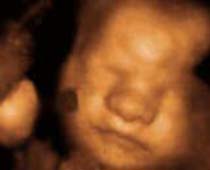

- Fetal Face Ultrasound Photos

- 3D Fetal Profile Ultrasound Scan Photos

- The Clinical Advantages of 3D and 4D Ultrasound

- Definition and Features of Four Dimensional Ultrasound

- Uses of 4D Ultrasound scan

- 4D Ultrasound Scan Fetal Video Clips